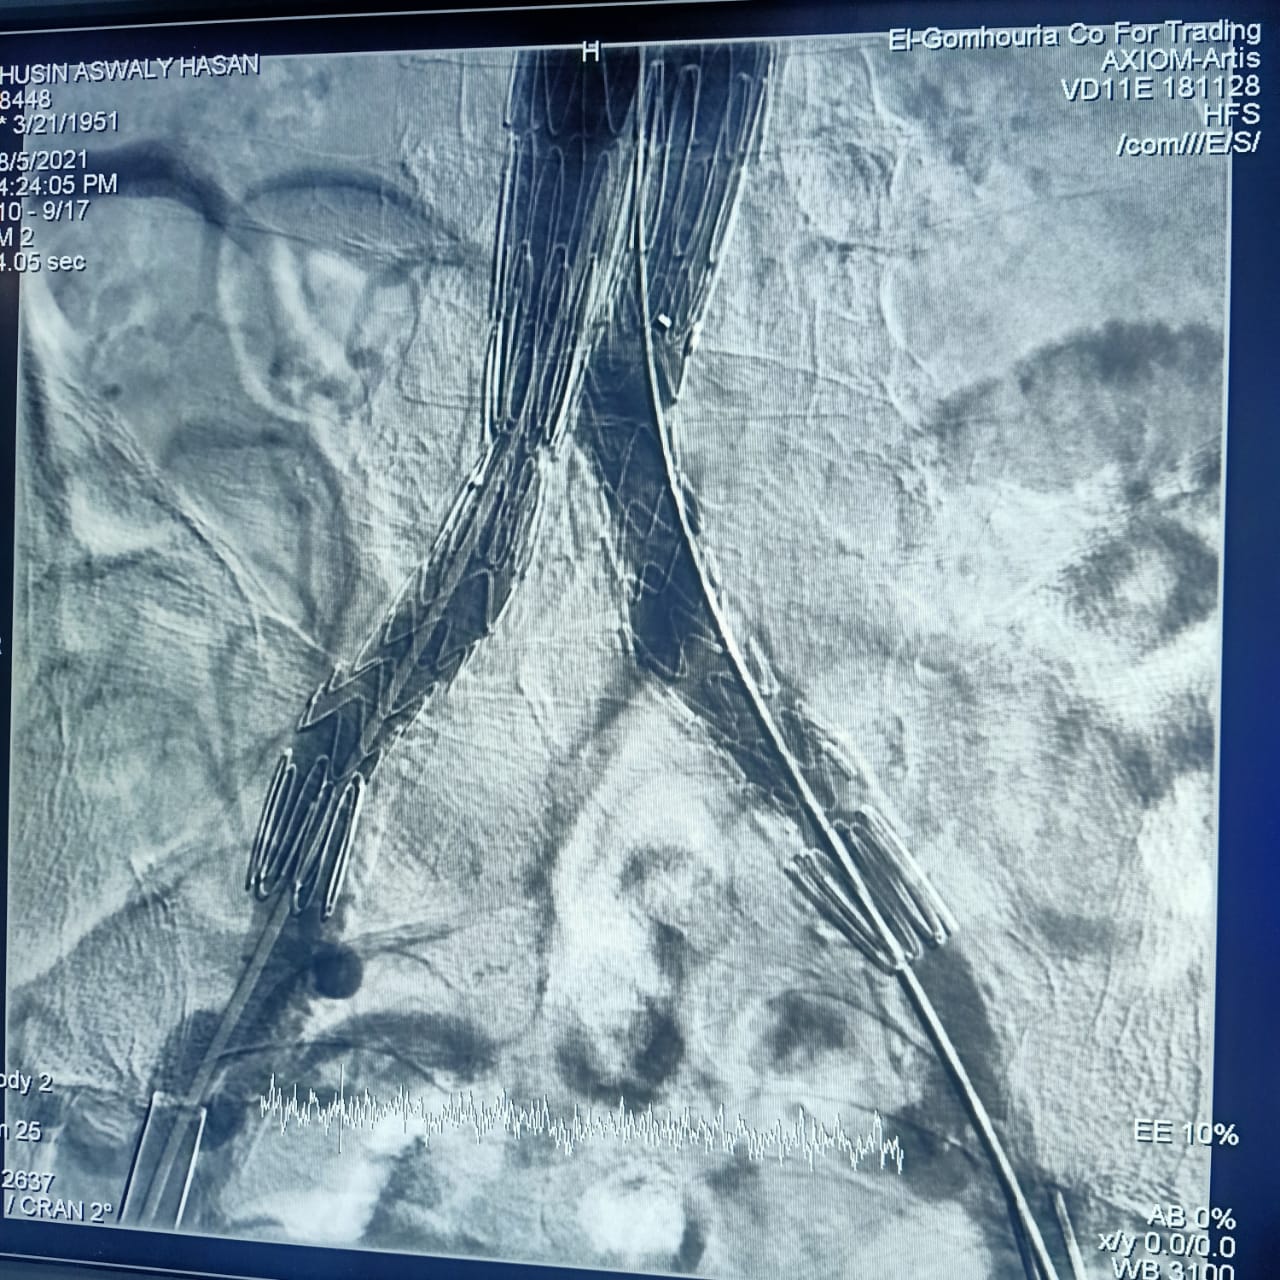

وأشارت هيئة الرعاية الصحية، أن CERAB، EVAR هي من أحدث التقنيات العلاجية لأمراض تمدد وانسداد الشريان الأورطي البطني والحرقفي (بدون جراحة)، من خلال علاج تمدد الشريان الأورطي البطني عن طريق القسطرة باستخدام تقنية الدعامات المغطاة EVAR، وكذلك علاج انسداد الشريان الأورطي البطني والحرقفي عن طريق القسطرة باستخدام تقنية الدعامات المغطاة ذات المقاومة العالية للانسداد CERAB، وذلك وفقًا لأحدث ممارسات الصحة العالمية.

وتابعت الهيئة: أن العملية الأولى كانت لعلاج مُسِّن يبلغ من العمر 70 عامًا يعاني من تمدد بالشريان الأورطي البطني وتم علاجه باستخدام تقنية الدعامات المغطاة EVAR، بينما كانت العملية الثانية لعلاج مريض يبلغ من العمر 65 عامًا باستخدام تقنية الدعامات المغطاة المقاومة للانسداد CERAB، مشيرة إلى استقرار الحالة الصحية للمريضين وإجراء العمليات بنجاح على يد أمهر الأطقم الطبية والتمريضية في مستشفى طيبة التخصصي بالأقصر.

واستكملت الهيئة، أن الفريق الطبي الذي قام بإجراء العمليتين، يضم كلًا من مدرسي واستشاريي جراحة الأوعية الدموية وقسطرة الشرايين بجامعة أسيوط " د. عثمان محمود، د. أشرف النجار، د. هشام أبو العيون"، واستشاري التخدير والعناية المركزة د. سعيد متولي، إضافة إلى الفريق الطبي المعاون لهم بمستشفى طيبة التخصصي من فنيي الأشعة والتمريض.